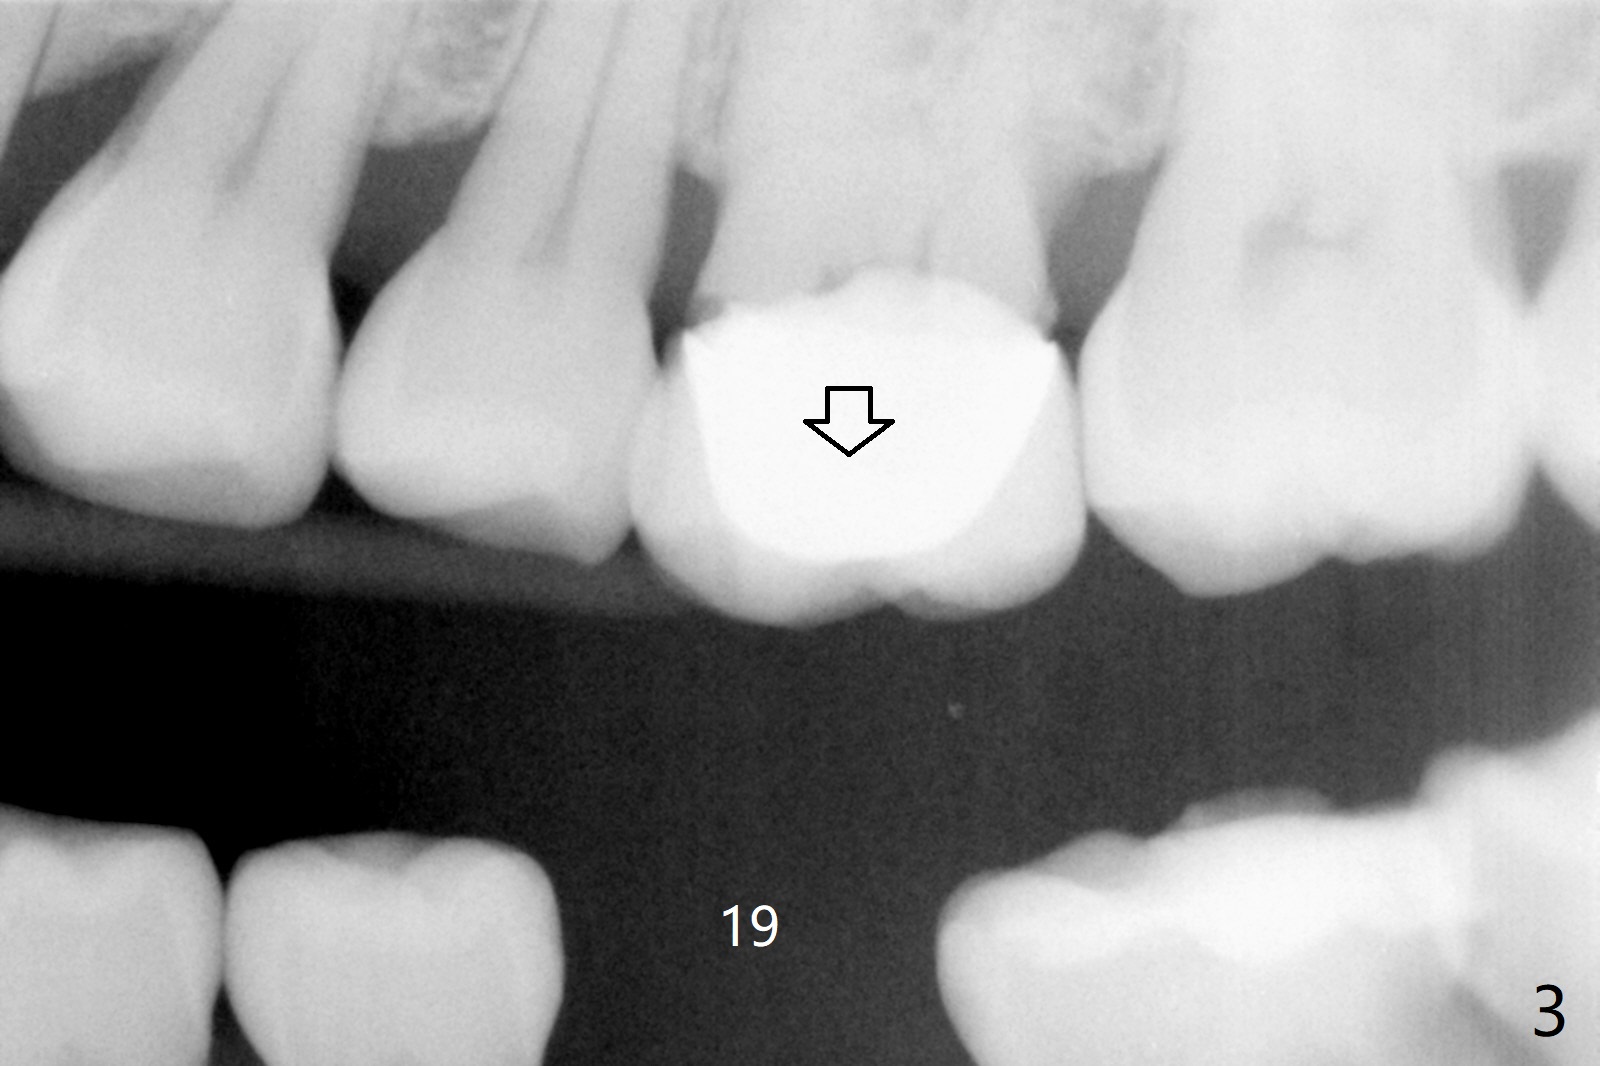

56岁女右上6植牙4年,牙冠松动两次,基台断裂一次,一直不肯做左下6植牙(图一,二,四),对合牙长长(图三:箭头;图五),因为害怕神经(图一:红虚线)损伤,导板已经介绍。IBS No Caries Xin Wei, DDS, PhD, MS 1st edition 11/20/2020, last revision 11/22/2020